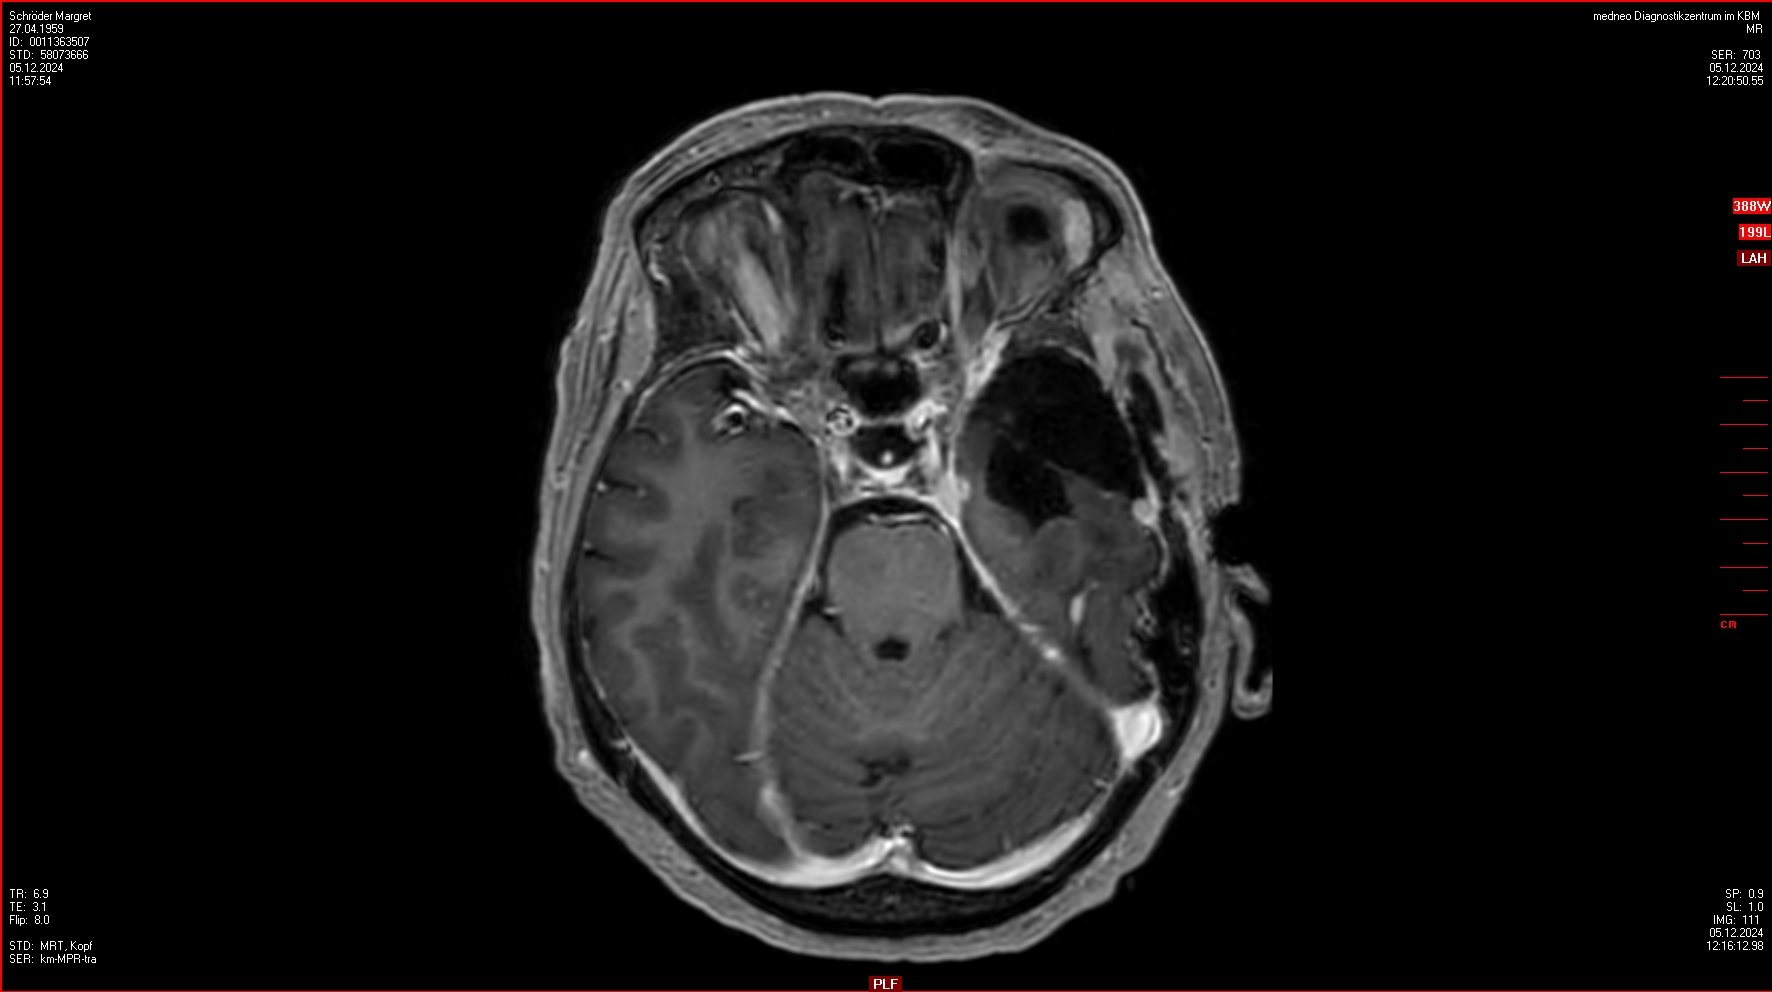

04.12.2024

OP im Krankenhaus Bremen-Mitte: 4 Menigeome (WHO III) entfernt, einige weitere verbleiben.

Ein ausführlicher Bericht von der OP findet sich hier.

23.01.2025

Gamma-Knife Behandlung imICERA Hamburg

4 Menigeome werden bestrahlt.

Ein weiteres Rezidiv wird entdeckt aber nicht bestrahlt. Aber dieses ist in den Folge-MRTs verschwunden.